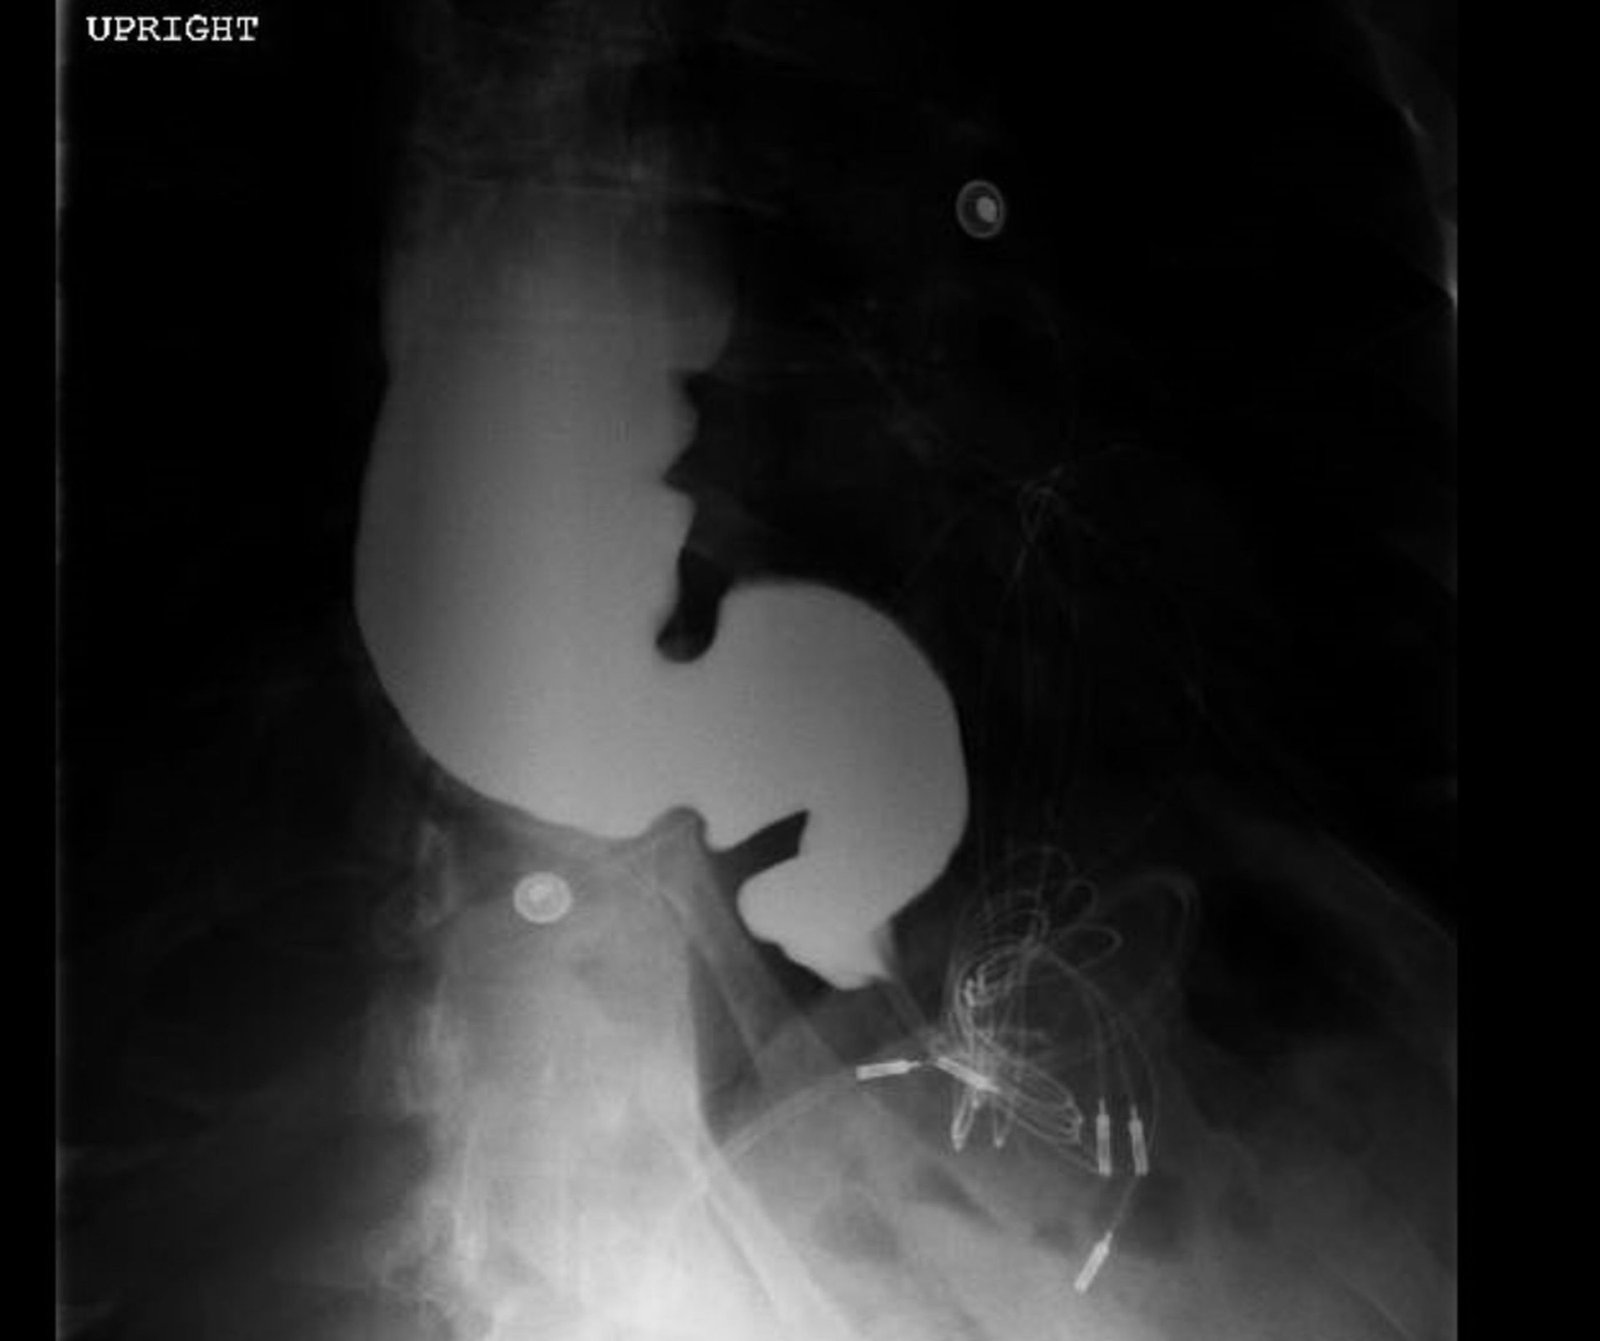

The chest X-ray demonstrated a markedly widened mediastinum (red brackets), raising concern for thoracic aortic aneurysm/aortic dissection, which prompted labs and contrast-enhanced computed tomography (CT) of the chest. The CT revealed a dilated proximal esophagus that narrowed distally (yellow tracing and red arrow), with particulate material, mass-effect on the trachea (purple outline), and bilateral patchy opacities suggesting aspiration. Barium esophagram showed a drastically dilated esophagus filled with contrast (yellow arrow), terminating into the classic “bird’s beak sign” (red arrow) at the lower esophageal sphincter (LES). Esophageal manometry later confirmed achalasia, proving that widened mediastina can have unexpected etiologies.

Achalasia is a rare (prevalence ~0.3-9.5/100,000, increasing with age) digestive disorder characterized by denervation to the distal esophagus, promoting regional aperistalsis and tonic contraction of the LES.1-3 Achalasia most commonly presents as acute, simultaneous dysphagia to both solids and liquids, but can present as heartburn, regurgitation, or even unexplained cough.1-3 A dilated esophagus with narrowing at the LES (“Bird’s Beak Sign”) and delayed esophageal emptying on barium esophagram are pathognomonic for achalasia (sensitivity 90%, specificity 95%),4 as is distal aperistalsis with increased resting LES tone on high-resolution manometry (sensitivity 98%, specificity 96%).5 Pharmacologic LES relaxation may be trialed, but surgical myotomy is usually necessary.1,2,3,6 Our patient underwent laparoscopic Heller myotomy resulting in a dilated, aperistaltic esophagus with no evidence of obstruction and is being followed for continued GERD and dysphagia.